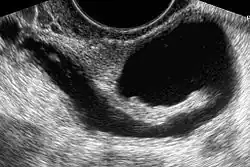

Sonohysterography using a balloon catheter (seen in the middle of the image)